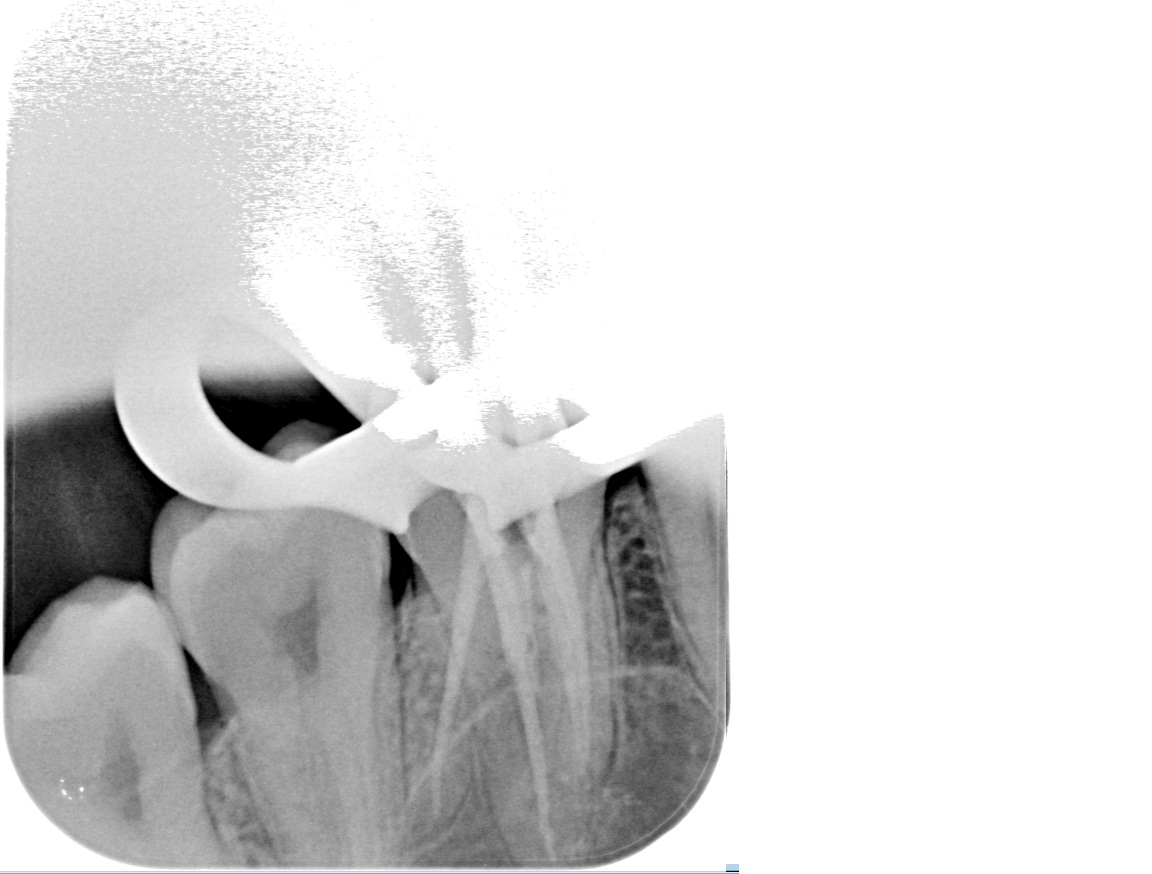

We use rotary nickel-titanium instruments, activated irrigation for deep disinfection, and modern bioceramic sealers for a dense, long-lasting seal. - Targeted diagnostics

We examine the tooth, test its response, and take focused images. When roots are complex or a previous treatment failed, a small 3D scan may be needed for mapping before we discuss and agree on the plan. - Anaesthesia and comfort